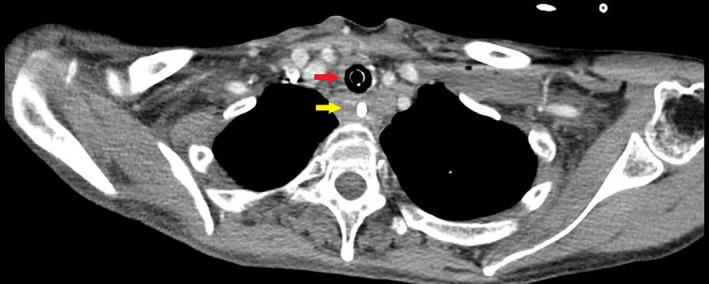

Iatrogenic tracheoesophageal fistula (TEF) through direct penetration of esophageal and tracheal walls is exceedingly rare. Body tissues sealing around the tube may result in delayed development of respiratory complications and diagnosis. Pneumomediastinum and pneumothorax may be absent. Maintaining the airway through TEF until tracheostomy resulted in a satisfactory outcome.